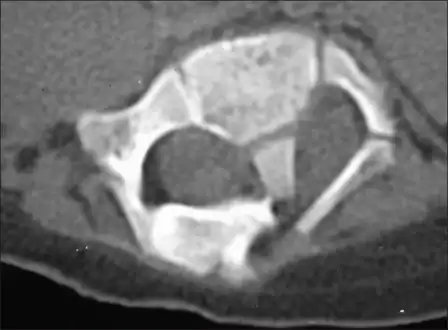

Adult presentation in diastematomyelia is unusual. With modern imaging techniques, various types of spinal dysraphism are being diagnosed in adults with increasing frequency. The commonest location of the lesion is at first to third lumbar vertebrae. Lumbosacral adult diastematomyelia is even rarer. Bony malformations and dysplasias are generally recognized on plain x-rays. MRI scanning is often the first choice of screening and diagnosis. MRI generally give adequate analysis of the spinal cord deformities although it has some limitations in giving detailed bone anatomy. Combined myelographic and post-myelographic CT scan is the most effective diagnostic tool in demonstrating the detailed bone, intradural and extradural pathological anatomy of the affected and adjacent spinal canal levels and of the bony spur.

Diastematomyelia usually occurs between 9th thoracic and 1st sacral levels of the spinal column with most being at the level of the upper lumbar vertebra. Cervical diastematomyelia is a very rare entity. The extent (or length of spinal cord involved) varies from one affected individual to another. In approximately 60% of patients with diastematomyelia, the two hemicords, each covered by an intact layer of pia arachnoid, travel through a single subarachnoid space surrounded by a single dural sac. Each hemicord has its own anterior spinal artery. This form of diastematomyelia is not accompanied by any bony spur or fibrous band and is rarely symptomatic unless hydromyelia or tethering is present. The other 40% of patients have a bony spur or a fibrous band that passes through the two hemicords. In these cases, the dura and arachnoid are split into two separate dural and arachnoidal sacs, each surrounding the corresponding hemicord which are not necessarily symmetric. Each hemicord contains a central canal, one dorsal horn (giving rise to a dorsal nerve root), and one ventral horn (giving rise to a ventral nerve root.) One study showed the bony spur typically situated at the most inferior aspect of the dural cleft. They advised that if the imaging appears to show otherwise, a second spur (present in about 5% of patients with diastematomyelia) is likely to be present.